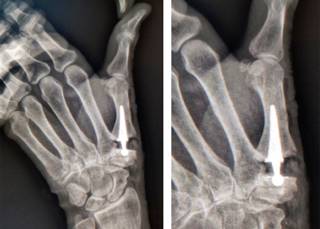

La artrosis trapecio-metacarpiana o rizartrosis es una patología que produce dolor, disminución de la fuerza y pérdida de destreza en la movilidad del pulgar, limitando la función global de la mano. Afecta a 20% de la población mayor de 50 años, principalmente en la mujer; provoca desgaste crónico y progresivo del cartílago que, en la mayoría de los casos, ocurre en ambas manos. Son típicos los episodios de dolor intenso en la base del pulgar que aumentan al movimiento y al realizar esfuerzos con la mano. Los movimientos del pulgar se reducen, lo que ocasiona rigidez progresiva. En los casos avanzados, se aprecia deformación por inestabilidad, subluxación y formación de osteofitos (Figura 1). La radiografía simple permite corroborar el diagnóstico utilizando la clasificación por estadios de Eaton y Littler (Tabla 1). Cuando el tratamiento médico conservador resulta ineficaz, se recurre a la cirugía. La finalidad de la prótesis trapecio-metacarpiana es eliminar el dolor y restaurar la longitud del pulgar, la fuerza y funcionalidad (Figura 2). El procedimiento quirúrgico por lo general se realiza de forma ambulatoria, consiste en eliminar la porción del hueso que está desgastada y reemplazarla con la prótesis, la recuperación es rápida y en dos o tres semanas se inicia la rehabilitación.